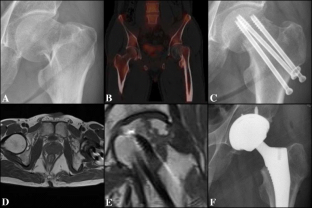

Fig. 1